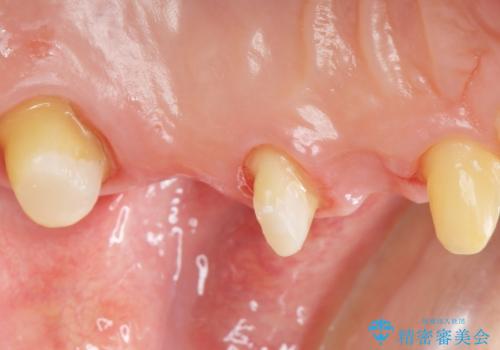

- 左上の歯ぐきが腫れていることを主訴に来院された患者様です。

精査したところ、歯ぐきが腫れている左上の小臼歯(左上4)は保存不可能な状態でした。

インプラント・ブリッジ・入れ歯の選択肢を提案させて頂いたところ、ブリッジをご希望されました。

保存不可能な歯(左上4)を抜去後、ブリッジによる補綴治療を行いました。